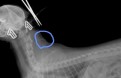

서울시수의사회 측은 이 캠페인을 하면서 “심장사상충은 모기가 동물의 피를 빨 때 감염되는 기생충”이라며 “개나 고양이의 심장과 폐동맥에서 5~7년 동안 살며 심장마비, 호흡곤란, 혈뇨, 복수 등의 증상을 일으켜 동물을 사망에 이르게 한다”고 밝혔습니다.